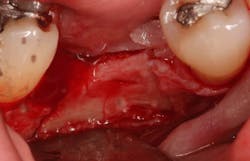

An osteotomy was then created, extending to the apical portion of the split ridge in preparation for implant placement. A bone-level tapered 4.1- x 12-mm implant was placed with a flat cover screw. A mixture of cancellous and cortical allograft particulate was infused with autogenous PRGF and packed around the implant on the mesial and distal aspects. The newly out-fractured buccal plate was positioned intimately adjacent to the buccal portion of the implant, and additional graft material was placed over the buccal plate to further augment the bone horizontally and reduce the risk of buccal-plate resorption during healing. A 25- x 30-mm Ossix Plus membrane was soaked in saline for three minutes and trimmed to extend 3–4 mm beyond the confines of the bone graft and roughly 1 mm from the adjacent teeth.

After the photo was taken to demonstrate the membrane placement, a periosteal elevator was used to further push the membrane under the lingual flap so that it draped intimately over the graft. The partial-thickness flap preparation made during initial incisions allowed for coronal positioning for tension-free primary closure. A CV-5 horizontal mattress suture was used to bring the buccal and lingual flaps together, and closure was completed with interrupted sutures.